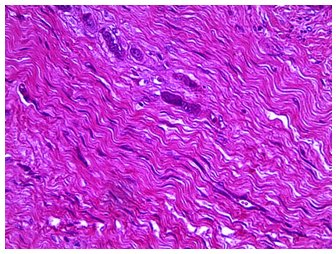

Caso 1. Microscópicamente, en los nódulos examinados se observó tejido fibroso muy desordenado, fibroblastos notoriamente polimórficos, alargados u ovalados y algunos de ellos con núcleos hipercromáticos, se notaron algunas figuras mitóticas de fibroblastos, así como algunas de estas células multinucleadas (figura 4) y bastante cantidad de componentes de la matriz extracelular. Otra característica histopatológica de este caso, fue la presencia de focos de necrosis del tejido tumoral de apariencia amorfa y de tonalidad azulina debido al proceso de calcificación (figura 5). En los ganglios linfáticos muestreados se observó infiltración de tejido tumoral fibrosarcomatosa con características similares a los hallazgos en los nódulos tumorales principales, pudiendo distinguirse algunas zonas de tejido linfoide, con apariencia relativamente normal rodeando los micronódulos malignos, se observaron, también, zonas de necrosis en proceso de calcificación distrófica.

Caso 1. Imagen microscópica de fibrosarcoma, obsérvese fibroblastos con núcleo hipercromático, alargado u ovalado y algunos fibroblastos multinucleados (H-E, 40x)

Caso 1. Imagen microscópica de fibrosarcoma, nótese zonas de necrosis en proceso de calcificación rodeadas de fibroblastos anaplásicos (H-E, 40x)

La apariencia histopatológica de tejido fibroso pobremente diferenciado conformada por fibroblastos que adoptan formas muy alargadas en algunos casos y ovaladas en otros casos, rodeadas de una matriz extracelular de gruesos haces de fibras, como se observó en ambos casos reportados, son características de los tumores malignos del tejido conectivo24,23. La presencia de fibroblastos conteniendo más de un núcleo y/o más intensamente coloreados o hipercromáticos, son características de los cánceres de tejido fibroso23,25,26, así como la presencia de algunas figuras mitóticas se observan en este tipo de tumores14,27 y son particularidades que se observaron en estos dos casos. Sin embargo, en el caso 1, motivo de este reporte, fue la presencia de numerosos focos necróticos, en algunos de los nódulos, con apariencia histopatológica amorfa adoptando diversas tonalidades azulinas denotando un evidente proceso de calcificación distrófica, este tipo de lesiones necróticas en los tumores malignos, generalmente se deben a la hipoxia y/o anoxia por la deficiencia de angiogénesis en la masa neoplásica28,29,30.